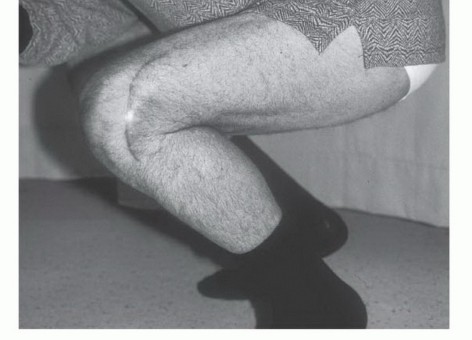

صعوبة الحركة أو العرج:

- التأثير: إذا كان الورم يؤثر على مفصل قريب، فقد يسبب صعوبة في تحريك هذا المفصل أو العرج إذا كان الورم في الساق.

| صعوبة الحركة/العرج | تقييد حركة المفصل القريب من الورم، أو عرج إذا كان الورم في الساق. | يؤثر على جودة الحياة والوظيفة اليومية. |

الجراحة الحافظة للأطراف (Limb Salvage Surgery):

تهدف إلى إزالة الورم مع الحفاظ على الطرف المصاب. تتضمن إزالة الجزء المصاب من العظم واستبداله بطعم عظمي، أو مفصل صناعي، أو طرف اصطناعي داخلي (Endoprosthesis). تتطلب مهارة جراحية عالية وتخطيطًا دقيقًا.

- حفظ الأطراف: يقلل بشكل كبير من الحاجة إلى الجراحات الواسعة أو البتر.

- نتائج وظيفية ممتازة: يحافظ على وظيفة الطرف المصاب ومظهره.